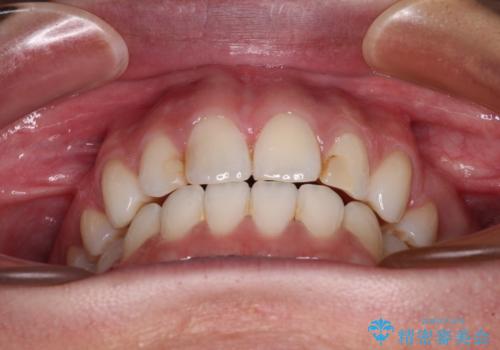

- くちばしのような前歯の突出感を気にして来院された患者様です。

上下左右第一小臼歯4本を抜歯して、積極的に口元を引っ込めるよう、ワイヤー装置にて矯正治療を行うこととしました。

抜歯矯正を行ったことで、顎先のつっぱり感や口元の閉じにくさを解消することができました。